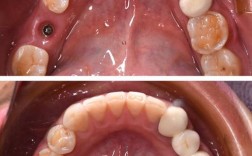

相比活动假牙、固定桥,种植牙被称为“人类的第三副牙齿”,优势更贴合中老年人的需求,它通过手术将人工牙根(种植体)植入牙槽骨,待骨结合后安装牙冠,能像真牙一样扎根在口腔里,咀嚼效率可达90%以上,几乎能恢复天然牙的咬合功能,而且种植牙不磨损邻牙,自洁性好,方便清洁,使用寿命也较长,维护得当能用十几年甚至更久。